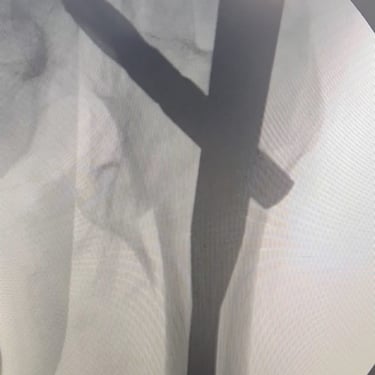

Gallery